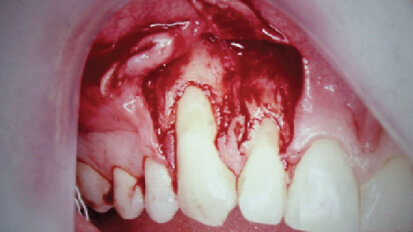

Horizontální augmentace kosti

Dr. Riz Syed hovoří o významu augmentace kosti na poli implantologie a některých možnostech léčby. Dentální ...

Kde končí parodontologie a nastupuje implantologie

Ošetření parodontu poskytuje nejen dobré orální zdraví, ale je také základním kamenem pro ...

Překrytí gingiválních recesů se stalo předvídatelné díky použití resorbovatelných bariér

Gingivální recesus je definován jako umístění nebo přemístění marginální gingivy ...